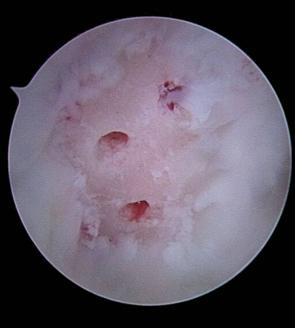

Fig. 1.14. Imagini artroscopice - leziuni osteocondrale stadiu IV A si B ICRS la nivelul condilului femural |

2.2.1.2.3. Microfracturile Steadmann

Aceasta tehnica este in prezent larg folosita, utilizeaza niste tepuse mici (similare cu brose K indoite) cu ajutorul carora se produc perforatii in osul subcondral (fig. 4.2). Numeroase studii clinice au confirmat valoarea acestei tehnici [40].

Fig.4.2 Imagini artroscopice. Microfracturi Steadmann pentru o leziune st IV A ICRS a condilului femural. In imginea 2 se observa perforatiile singerinde |